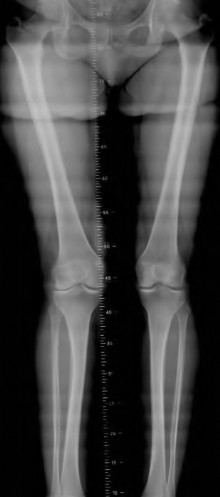

A 65-year-old woman with painful knee arthritis and the deformity seen in Figure A, is scheduled to undergo a total knee arthroplasty. All the following are risk factors for a post-operative peroneal palsy EXCEPT:

Figure A demonstrates and AP radiograph of the knee showing end-stage arthritis with severe lateral compartment narrowing.

The radiograph seen in Figure A reveals varus alignment of the knee, with medial tibial deficiency; from this X-ray the patient appears to have unicompartmental arthritis. Treatment options for unicompartmental arthritis include high tibial osteotomy, interpositional arthroplasty, unicondylar knee replacement and total knee replacement. Interpositional arthroplasty became popular in the 1950’s when early outcomes analysis seemed to indicate good results; long term follow up in one study found 0/12 excellent results, with all patients requiring conversion to TKA. This procedure is no longer recommended due to the poor long term outcomes.

While an osteotomy is still used for young and active patients, unicompartmental or total knee arthroplasty have largely replaced this treatment in older patients. Advantages of UKA and TKA include more predictable relief of pain, quicker recovery, and better long-term results. Criteria for UKA include limited unicompartmental disease, no more than a fixed 10 degrees of varus or 5 degrees of valgus deformity from neutral and an intact anterior cruciate ligament with no signs of medial lateral subluxation of the femur on the tibia; this patient is therefore not a good candidate for this procedure.

Total knee arthroplasty can be used to provide predictable pain relief in a patient with unicompartmental and tricompartmental degenerative disease and varus malformation of the knee and for this patient is the best option.